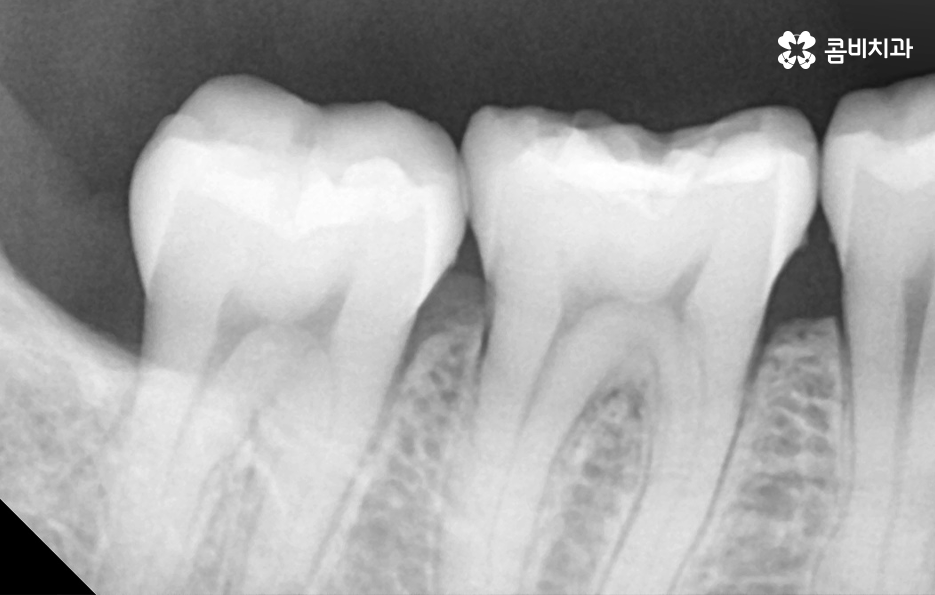

어금니 레진으로 치료 했던 부위의 주변에 검게 변색되었어요. 그리고 주변이 깨졌어요

보철 치료 후의 2차 충치 문제는 사실 아말감 뿐 아니라 어떤 보철물이든지 주의해야 할 점이며 보철물 자체나 주변 치아가 깨지거나 마모되어 2차 충치가 진행되기도 하지만 오래된 보철물의 접착제가 녹아서 2차 충치로 이어지는 경우도 있기 때문에 보철물의 수명과 교체 주기에 따라서 주기적으로 재치료를 하는 것이 2차 충치에 대한 우려를 예방하는데도 중요할 수 있어요

어금니 레진 치료 후에 레진 자체가 깨지거나 주변 치아가 깨진 경우에는 당장 안아파도 치과에서 재치료를 받는 것이 추가적인 파절을 예방하고 치아 내부로 충치가 발생되는 것을 예방할 수 있으며 특히 주변이 검게 변색되는 경우에는 착색인 경우도 있지만, 2차 충치가 이미 진행된 경우가 많기 때문에 통증과는 무관하게 치과 방문을 권하고 있어요

특히 치아 신경치료로 이어지거나 치아 뿌리 쪽에 충치가 깊어지면 치아 수명이 급격히 저하되고 발치로도 이어질 수 있다는 점에서 현재 어금니 레진 교체에 대한 고민을 한다면 현재 치아 상태에 적합한 치료도 제때 잘 받아주시길 바라며 무엇보다 보철물 관리에도 힘써서 비슷한 문제가 재발하지 않도록 주의하시길 바라고 있어요